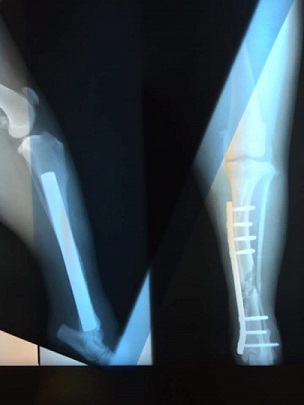

Heres your baby Chanders Mom

(IMG_2872.JPG)

(part0.jpg)

(part0 (1).jpg)

(part0 (2).jpg)

She was a little too rambunctious earlier---wanted to chase Luca across the hardwood floor when it was time to go out to pee. . . She's never off leash but she was spinning wheels trying to get Luc!!!! Lord she doesn't realize how much that dang back leg is worth now